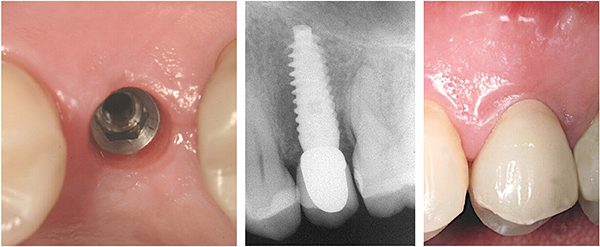

BONE PLATFORM SWITCHING

The particular morphology of the collar (Reverse Concave Neck – RCN) increases the implant contact surface area with the bone and preserves a greater proportion of bone and periosteum.

The taper and concavity of the collar guarantees a gentle contact and reduced stress on the crestal cortical bone preventing undesired vascular compression.

Platform Switching – The prosthetic connection leaves constant horizontal progressive space for the biological width, limits bone resorption, stabilizes the soft tissue and ensures excellent papillary aesthetics.